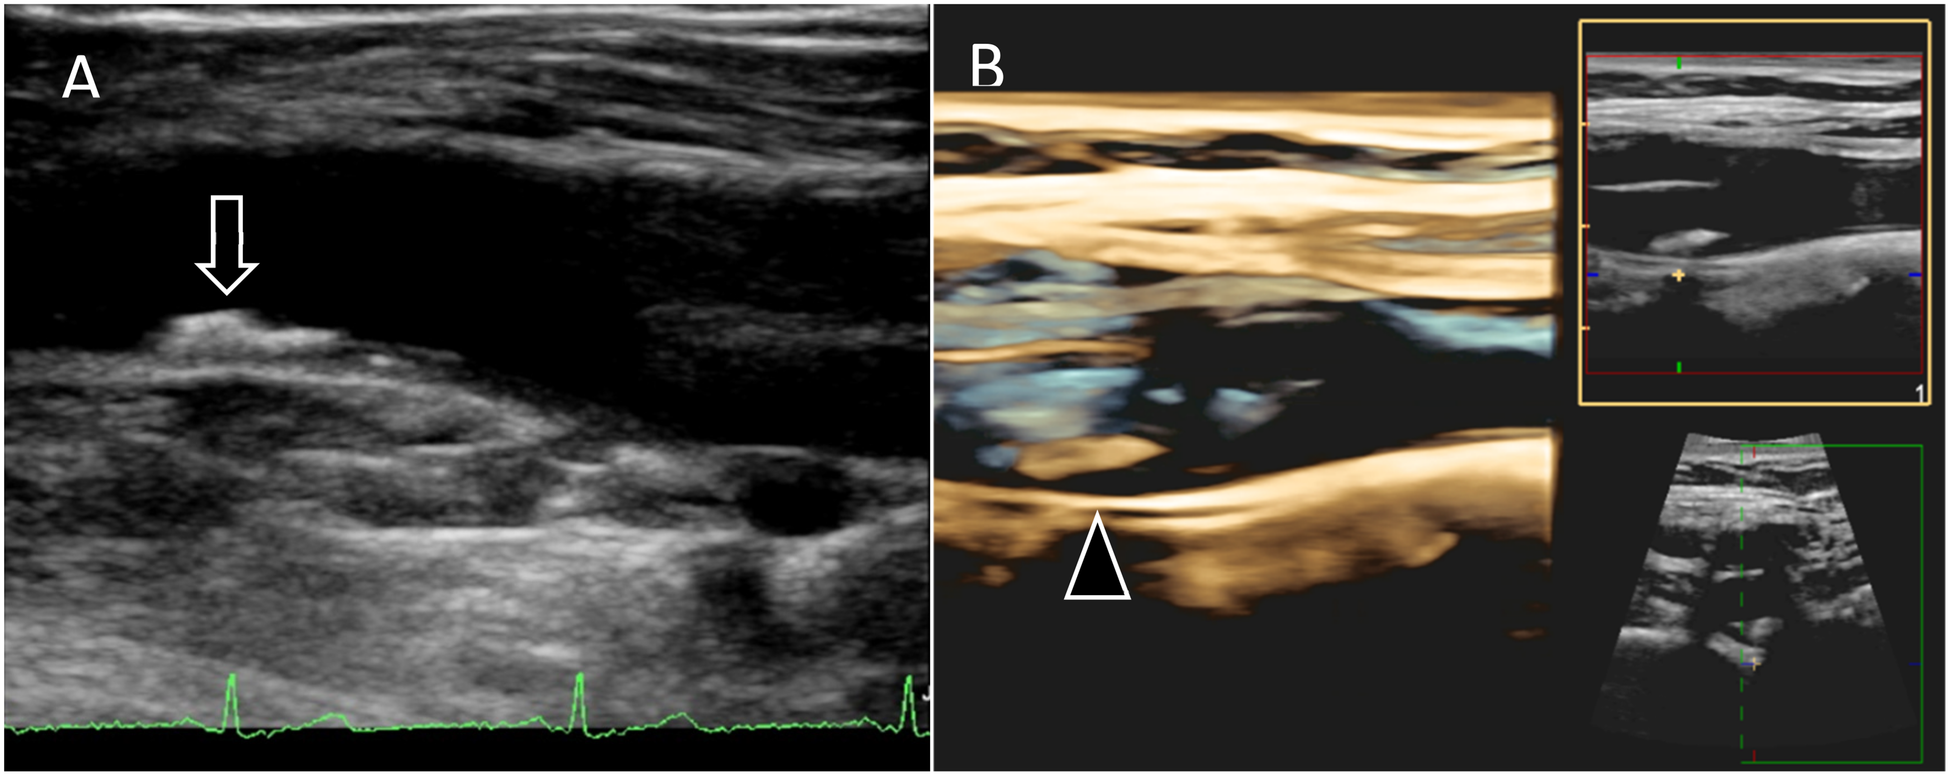

Vascular ultrasound imaging will be carried out using Philips EPIQ Elite 7.0.5 and the protocol includes 2D VUS of the carotid, aorto-iliac and femoral territories (cross-sectional and longitudinal images) and 3D VUS of any plaque (volume set) with an approximate examination time of 40 min (Figure 2). Imaging analysis will include plaque presence, thickness, volume and degree of stenosis (5). Strain-rate measurements of the carotid cross-sectional image will also be assessed to increase our understanding of the elastic properties and function of the arterial walls providing potential information on arterial health status by analyzing distensibility/compliance coefficients, b-stiffness index, circumferential strain/strain rate, peak radial velocity (Figure 3) (32).

Figure 2

2D and 3D vascular ultrasound (A) 2D images of femoral artery showing atherosclerotic plaque (arrow) located in the common femoral artery prior to bifurcation. (B) 3D images of carotid artery bifurcation showing atherosclerotic plaque (arrow head) located in internal carotid artery.